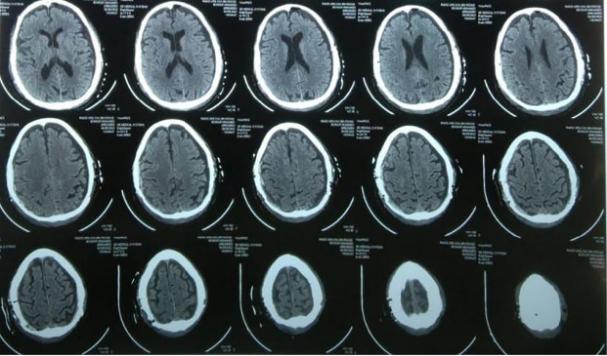

选择左侧作为第一步是为了给优势大脑半球减压。患者在手术室拔管,恢复意识,GCS评分为15/15,无感觉运动障碍。后续CT扫描令人满意[图3]。

图3、术后CT